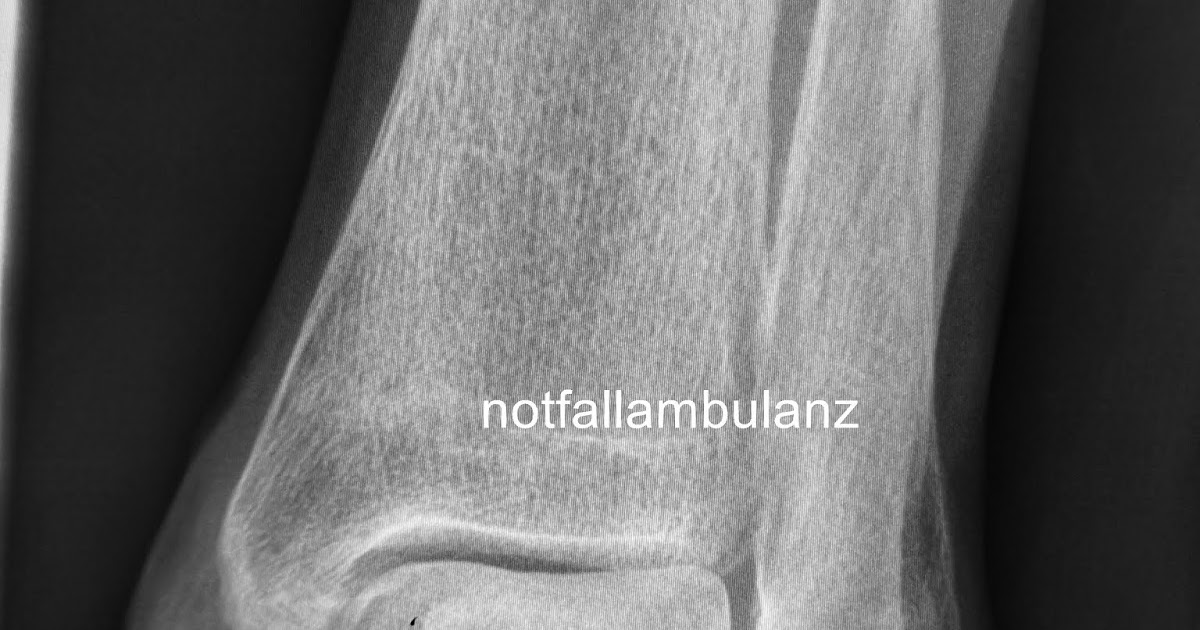

Brennpunkt Notaufnahme Fall 70 Eine einfache

Brennpunkt Notaufnahme Fall 70 Eine einfache Weber C Fraktur?

Ankle fracture Weber C Image